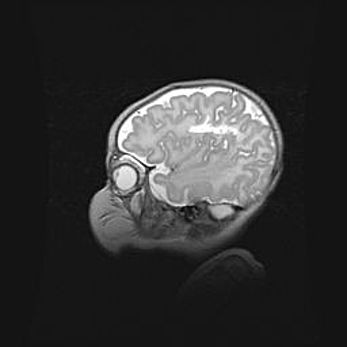

Сообщающаяся гидроцефалия. Кистозная энцефаломаляция головного мозга.

Возраст: 3 месяца 4 дня

Вес: 3100 г

Пол: женский

Окружность головы: 34 см

Срок гестации: 31 неделя

Кистозная энцефаломаляция головного мозга - одна из форм поражения головного мозга в детском возрасте. Характеризуется возникновением множественных и распространённых кист в коре, белом веществе и подкорковых образованиях головного мозга у плодов, новорождённых и детей раннего возраста. Развитие кистозной энцефаломаляции связано с внутриутробной асфиксией и гипотонией, родовой травмой, тромбозом синусов, пороками развития сосудов, инфекциями, сепсисом и другими причинами. Наиболее значимые инфекционные агенты: вирусы простого герпеса, цитомегалии, краснухи, токсоплазмы, энтеробактерии, золотистый стафилококк и другие.